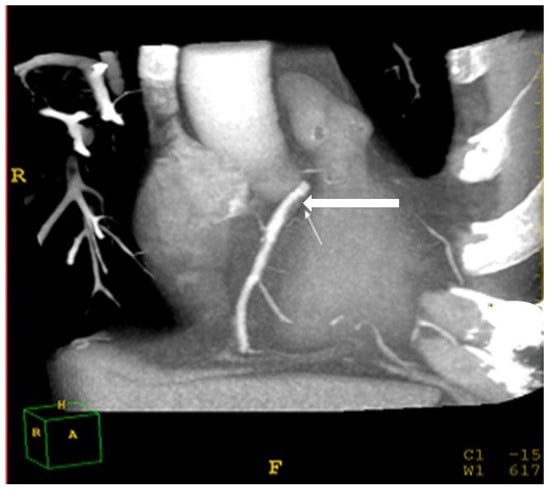

2.7. Assessment of Coronary Atherosclerosis

Identifying coronary atherosclerosis was performed using a cardiac CT protocol. A bolus of 70–90 mL iomeprol (400 mg/mL; Iomeron 400; Bracco, Milan, Italy) contrast medium was injected intravenously (4 mL/s) followed by a 50 cc bolus of saline, placed in the antecubital vein with an 18-gauge catheter. The scan delay was determined using an automatic bolus test in which the ROI was located on the ascending aorta. Patients were instructed to maintain an inspiratory breath hold while acquiring both CT data and electrocardiogram (ECG) traces. A 64-row scanner with slice thickness of 0.625 mm was employed. Beta blockers (Propranolol, 20 mg tab) were given orally if there was >70 beats per minute (BPM) during resting heartrate. If the heartrate was >80 BPM, the patient was excluded from the study. Raw image datasets from all acquisitions were analyzed by two independent specialists (a cardiologist (A.M.) and a radiologist (L.A.), both with over 20 years of experience) who were unaware of the hepatic and lipid profiles of the patients. The two specialists visually graded the degree of stenosis and plaque composition. The stenosis was considered significant if over 50% occlusion of the arterial lumen was present [25,26]. Coronary artery Brilliance Philips Medical Systems, USA disease was defined as a stenosis of over 50% in at least one major coronary artery (Figure 5).

Figure 5.

Cardiac computed-tomography section showing a major coronary artery (white arrow).